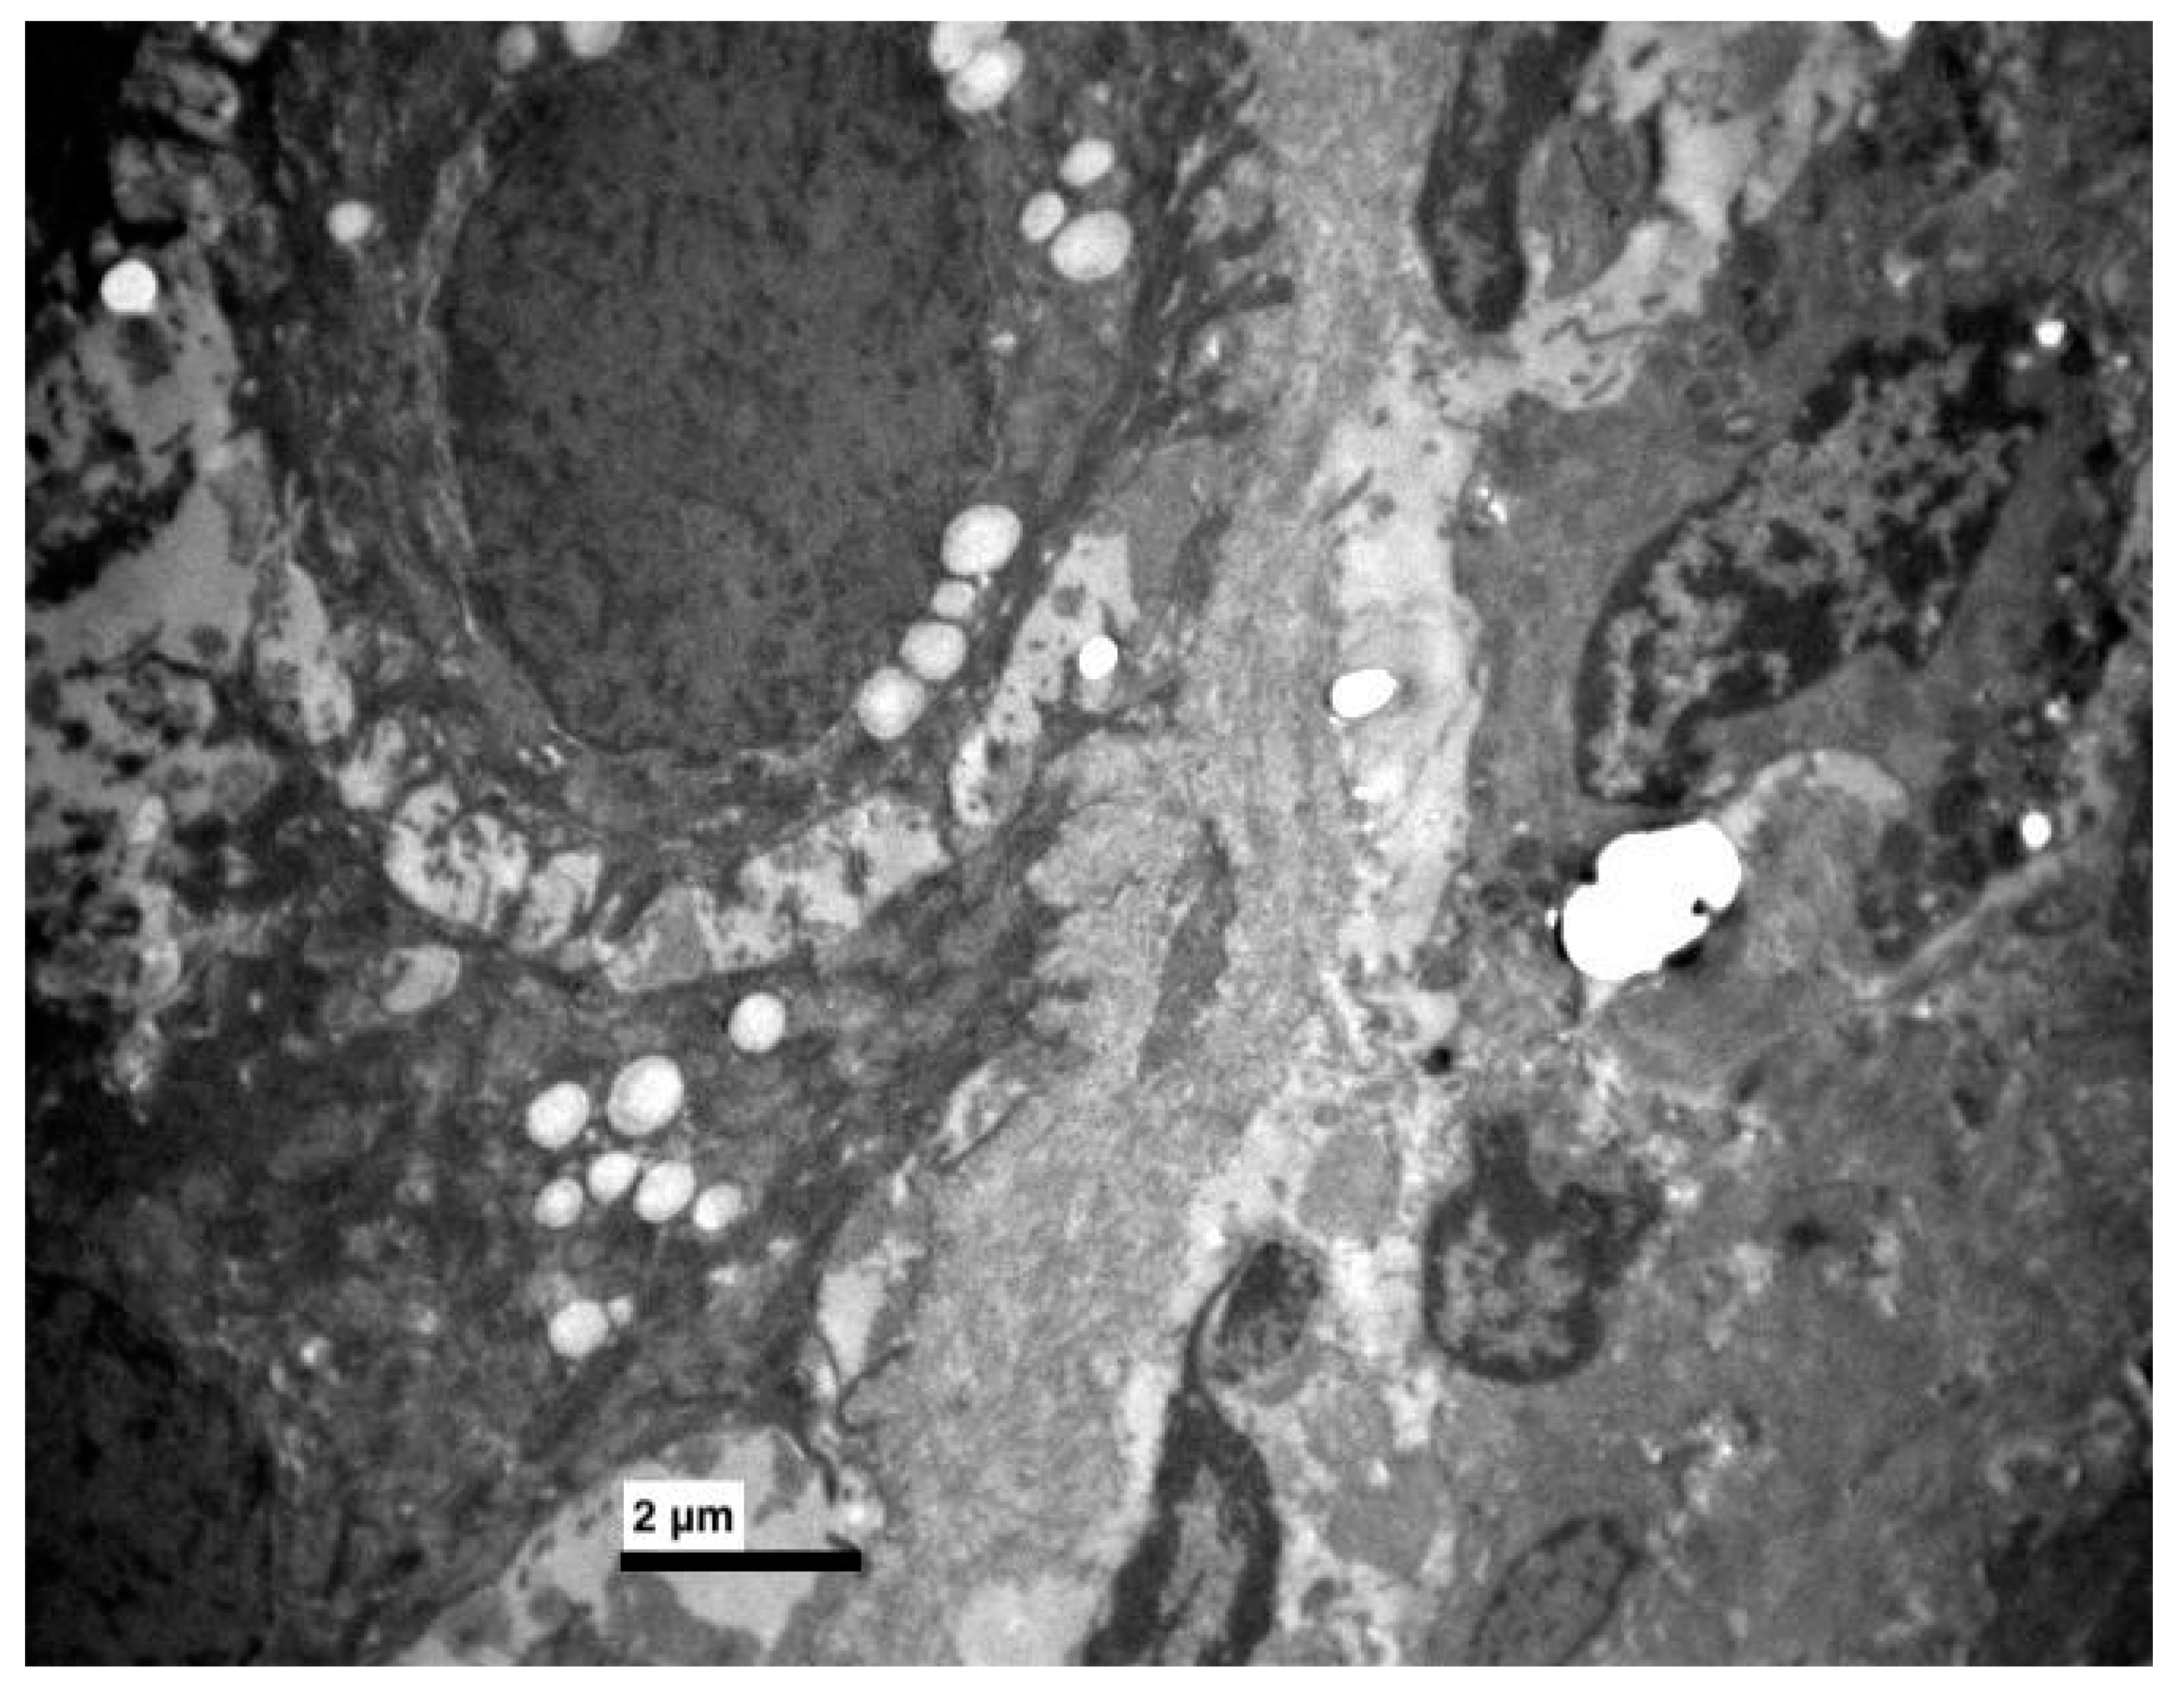

3. Results